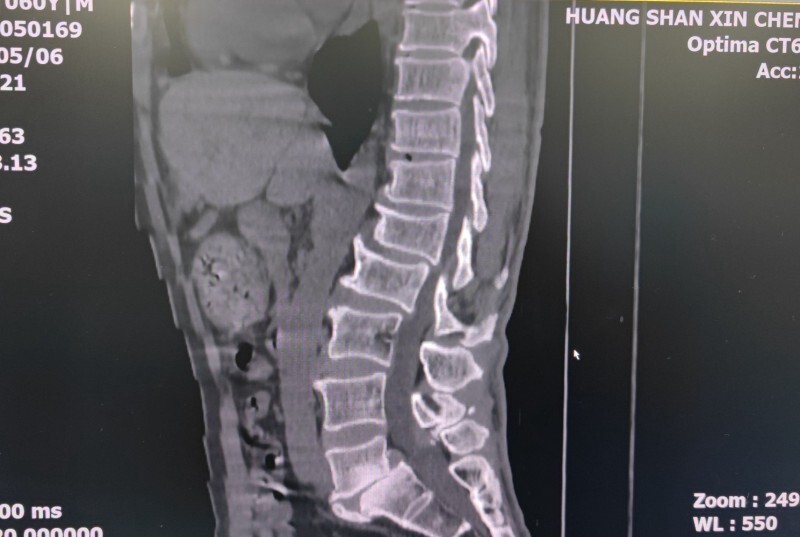

术前片子

方先生,60岁。腰背部疼痛反复发作5年有余,期间也曾在多家医院就诊治疗过,效果不太明显,最近因为病情加重,慕名来我院就诊。5月14日新晨医院骨科为他实行了一台特殊的手术,骨科专家们特别邀请到一名“硬核医生”——机器人“天玑”参与其中。手术进行得十分顺利,这台手术是黄山新晨医院完成的第二台机器人辅助下手术,也是黄山首例“天玑”机器人辅助微创脊柱手术。